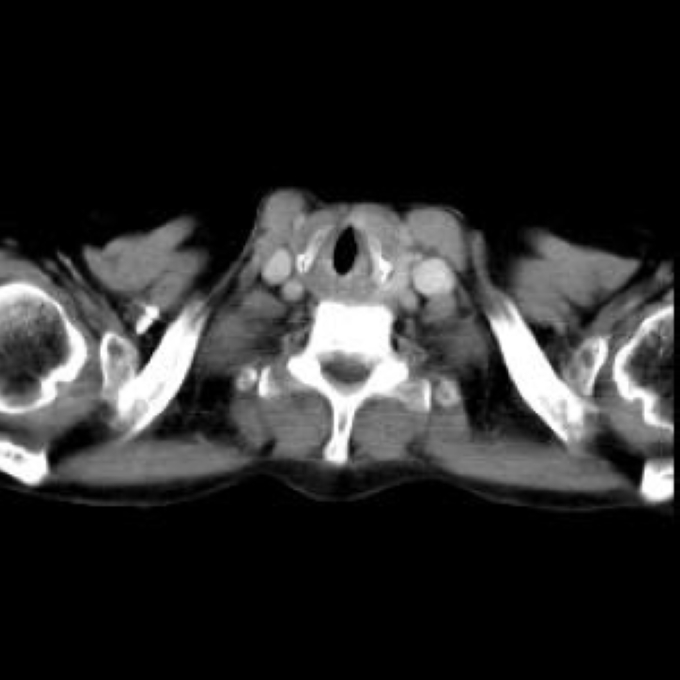

Arteria lusoria.

56 year old patient with dyspagia. A tumor of soft tissue was described in upper mediastinum on plain X-ray of the thorax. What is this mass in the upper mediastinum?